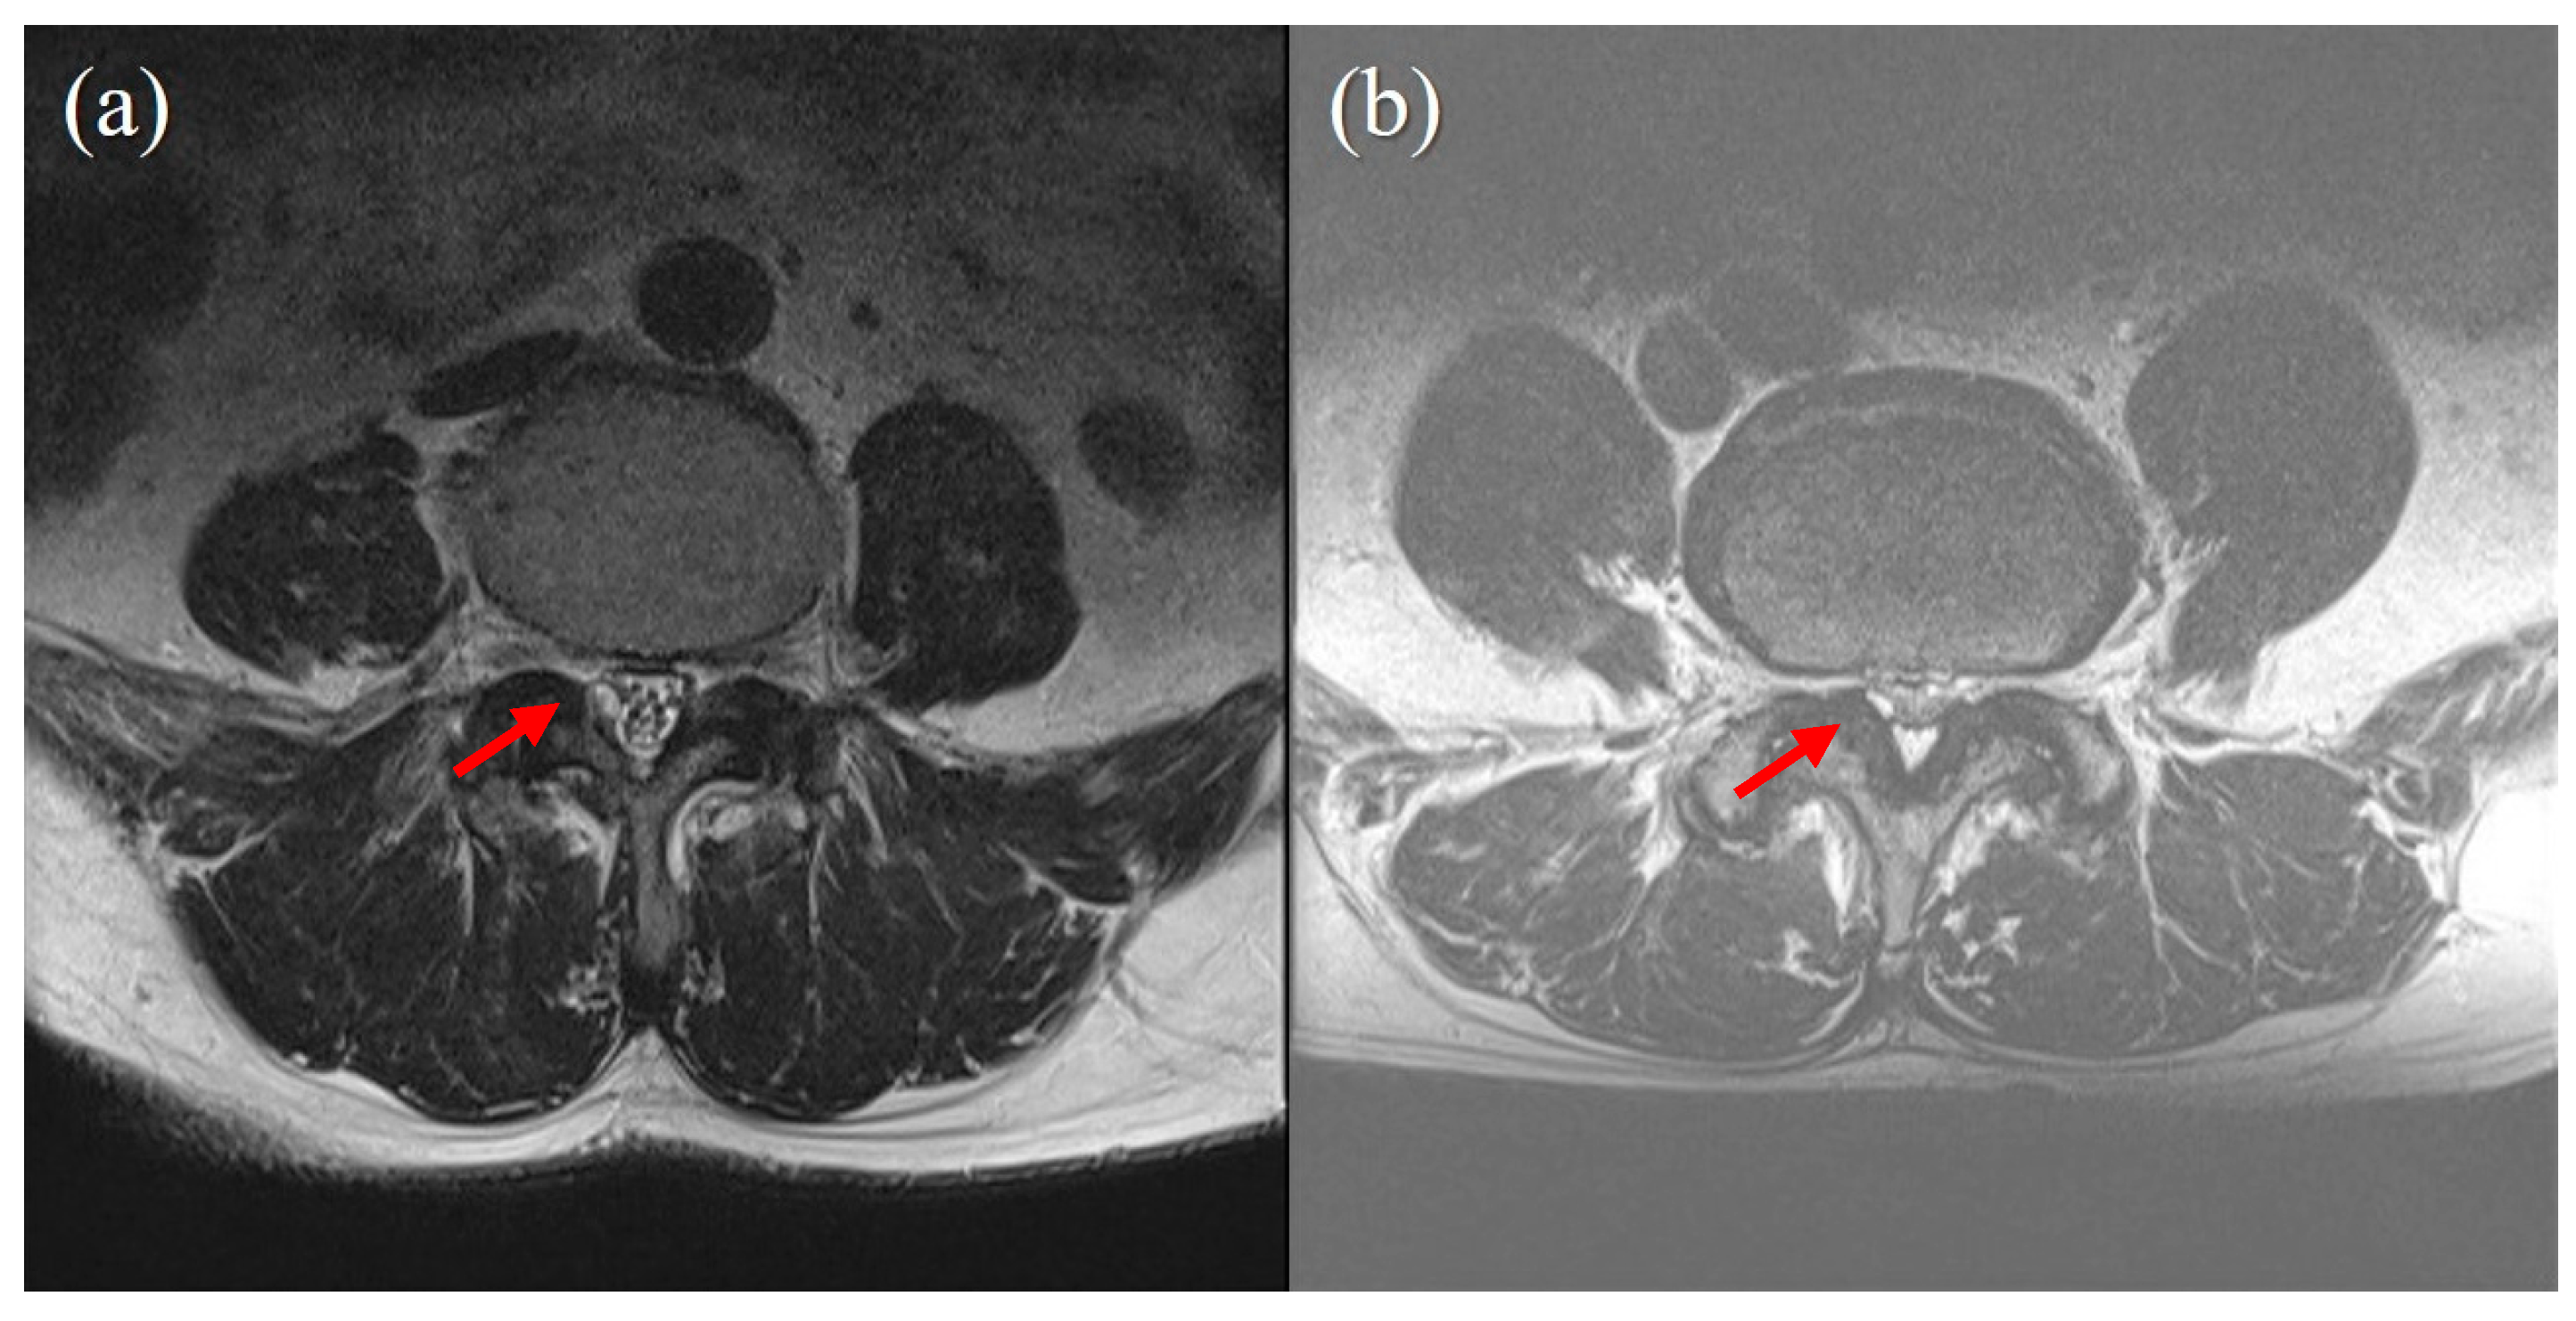

Figure 2. Cyst size does not correlate with success of percutaneous epidural neuroplasty. (a) case of successful treatment with percutaneous epidural neuroplasty. A 3 mm-sized juxtafacet cyst on the Rt posterolateral spinal canal connected to a facet joint. Ther was no visible CSF signal, and no rootlet was recognizable (Schizas grade C). (b) A case of failed percutaneous epidural neuroplasty, for which surgery was eventually performed. A 2 mm-sized juxtafacet cyst in the same location as (a). A CSF signal and rootlets were visible (Schizas grade B).

In the present study, we analyzed whether cyst size, pre-procedural VAS score, symptom duration before procedure, predisposing factors (hypertension, diabetes mellitus, antiplatelet or anticoagulant use), age, gender, and BMD were associated with procedure success. The degree of pain (VAS score) and duration before the procedure were not associated with the result of the procedure. The cyst size was also not associated with the procedure results (Figure 2). However, in the four patients who underwent surgery, the cyst size was smaller than in the patients who did not undergo surgery (5.82 mm vs. 6.42 mm).

Regardless of the cyst size, in cases where there was severe pressure on the cauda equina due to stenosis of the spinal canal, the outcome of neuroplasty was poor and often eventually led to surgery (p-value = 0.000). When the 4 patients who underwent surgery were compared with the 30 other patients, spinal stenosis was sufficiently severe to cause the obliteration of the CSF space, and posterior epidural fat on MRI corresponded to Grade C (no rootlets recognizable, no visible CSF signal but epidural fat present posteriorly) of the Schizas system [9]. Patients classified as Grade A or B had a significantly lower probability of undergoing surgery, and the probability that their symptoms would not worsen was significantly higher than in patients classified as Grade C (Table 2). The pathogenesis of a juxtafacet cyst is thought to be related to spinal degeneration caused by the motion of a spinal segment [10] and appears to be the final stage of the degenerative process of the lumbar spine [11]. One explanation for the failure of the neuroplasty of juxtafacet cysts in patients with severe spinal stenosis is because the disease occurs in the same or a consecutive segment as spinal stenosis. In addition, if the cyst was present at a level other than the L4–L5, the likelihood of surgery was significantly low (p-value = 0.003). Patients with diabetes were more likely to undergo surgery (p-value = 0.03; Table 3).